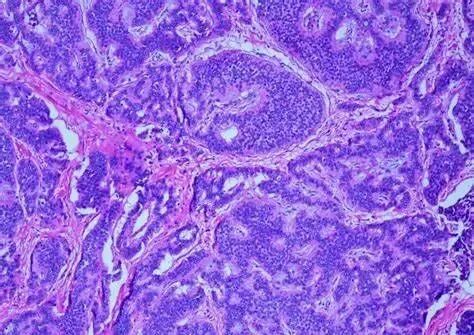

正常细胞转变为癌细胞的过程中,一开始更活跃地分裂。随着肿瘤的进展,已经转变为恶性的组织继续改变,恶性程度增加。肿瘤细胞开始分化,自身细胞的调节系统将不再能够控制发生的变化。最终,癌组织开始扩散转移。

肿瘤细胞起源于既往正常和健康的细胞。这些细胞通常围绕在肿瘤周围。病理学家使用“分化”一词描述癌细胞和周围正常健康细胞之间的差异,因为并非所有的癌细胞都相似。有些癌细胞与正常的健康细胞相似,而有些则差异很大。

简单地讲就是细胞长得越怪越不像正常的细胞它的分化就越低恶性程度就越高,它就越喜欢“调皮捣蛋”到处跑。

• 高分化:癌细胞与周围的正常细胞非常相似,有时很难区分二者之间的不同。uVs帝国网站管理系统

• 中分化:癌细胞明显异常,但与周围正常细胞的某些特性仍一致。uVs帝国网站管理系统

• 低分化:癌细胞明显异常,当低分化的肿瘤迁移至淋巴结,或身体其他部分时,可使用免疫组化分析等方法确定肿瘤的类型及起源位置。癌细胞移动到身体其他部位的行为称为转移。uVs帝国网站管理系统

• 未分化:癌细胞与身体内任何部位的正常细胞均不同。即使采用额外检测,病理学家也很难确定这类肿瘤的起源部位。uVs帝国网站管理系统

• 去分化:用于描述肿瘤由两种不同类型的癌细胞构成。第一类癌细胞与正常细胞非常相似。第二类癌细胞与正常细胞相似度很低,或不相似。uVs帝国网站管理系统

高分化和中分化癌生长更缓慢,更不可能扩散到身体其他部位。相反,低分化和未分化癌则更具侵袭性,生长更快,更易于扩散到身体其他部位。